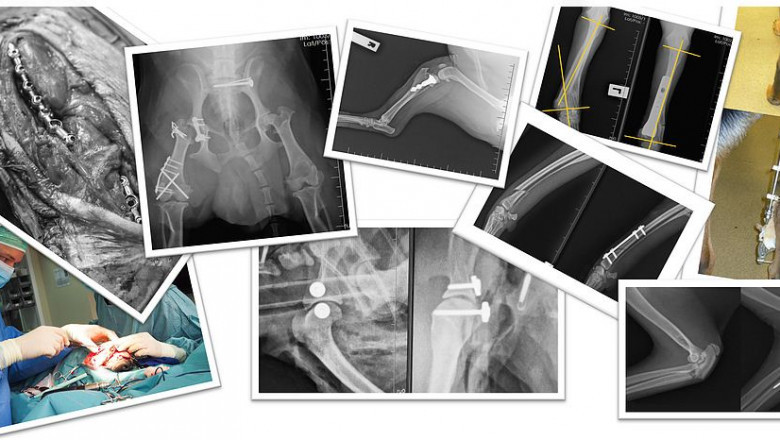

We provides pet orthopedic treatment singapore. Our caring and professional team are intensively trained to provide the best veterinary care for your pet.

We provides petorthopedic treatment singapore.Our caring and professional team are intensively trained to provide the bestveterinary care for your pet.